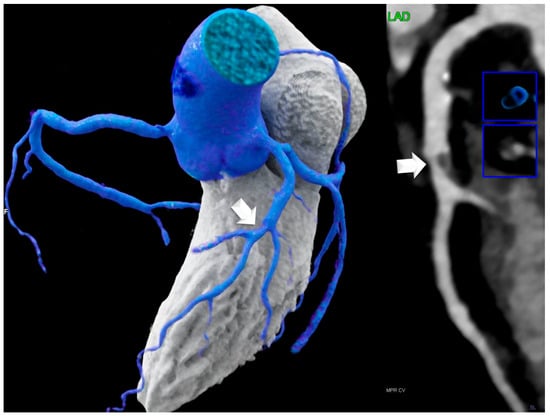

- Lipomatous hypertrophy of the interatrial septum (LHIS): This is defined as a mass-like lipomatous tissue infiltration of the entire interatrial septum from cranial to caudal, sparring the fossa ovalis, with a “dumb-bell” configuration with >than 5 mm width.The maximal width was identified on axial images and measured with a digital caliper. The maximal length was defined as the distance from the anterior to the posterior borders.